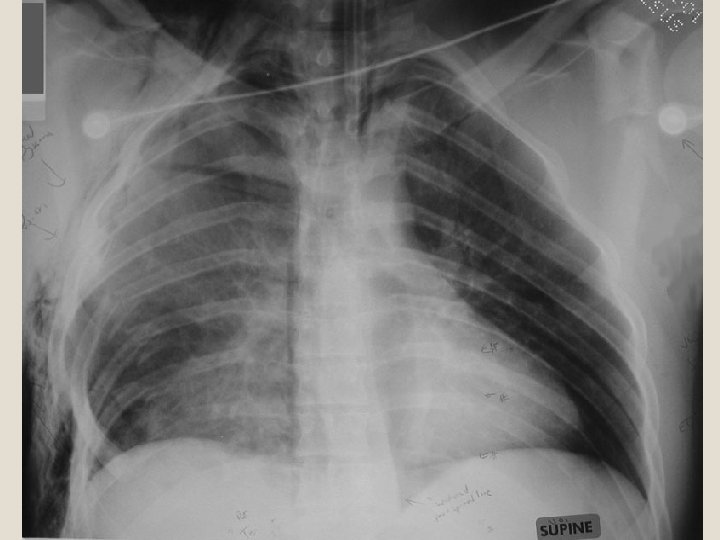

�Dengan foto toraks akan lebih jelas karena akan terlihat fraktur iga yang multipel, akan tetapi terpisahnya sendi costochondral tidak akan terlihat. �Pemeriksaan analisis gas darah yaitu adanya hipoksia akibat kegagalan pernafasan, juga membantu dalam diagnosis Flail Chest.